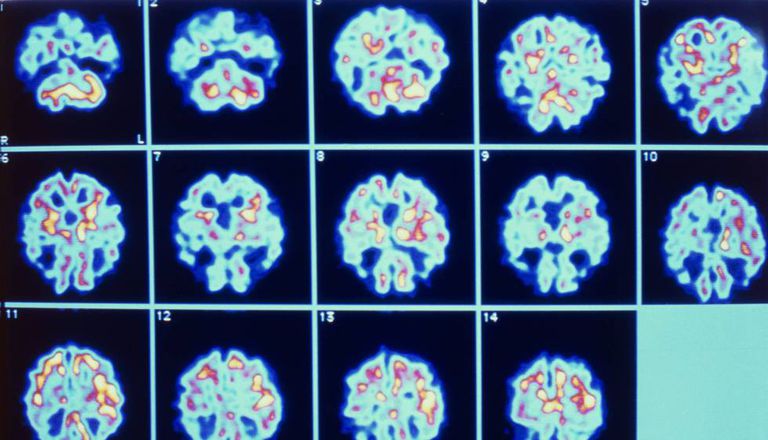

As primeiras alterações produzidas pelo Alzheimer ocorrem a nível bioquímico no tecido cerebral. É a acumulação de placas de proteína beta-amiloide (AB) no exterior dos neurônios e a formação intracelular de nódulos neurofibrilares de proteína TAU, os dois marcadores que aparecem nas fases mais iniciais da doença. A presença de placas de amiloide, detectadas através de técnicas bastante invasivas como a punção lombar e o dispositivo de neuroimagem PET (tomografia por emissão de pósitrons), mede o risco de doença de Alzheimer; o acúmulo de fios de TAU, também determinado via punção lombar e PET, é um marcador de dano cerebral ligado à morte dos neurônios. O problema é que a acumulação dessas proteínas não é totalmente determinante para o desenvolvimento de Alzheimer, pois também são encontradas em outras demências relacionadas ao envelhecimento.

De modo que o passo seguinte dos pesquisadores foi combinar os rastros bioquímicos deixados pela doença com outros marcadores de neuroimagem (como a volumetria, medida através de ressonância magnética) para afinar o diagnóstico precoce de Alzheimer. Nesse sentido, pesquisadores das universidades Complutense e Politécnica de Madri participaram de um estudo com o National Center for Geriatrics and Gerontology do Japão para detectar os primeiros sinais do Alzheimer com marcadores minimamente invasivos. O estudo, publicado na revista científica Brain, encontrou alterações nos padrões de atividade cerebral relacionadas à quantidade de placas de amiloide acumuladas no cérebro.

“Existem muitas doenças ocultas que têm os mesmo sintomas que o Alzheimer. Nós analisamos a atividade cerebral de idosos saudáveis e com deterioração cognitiva leve através da magnetoencefalografia (MEG), uma técnica que detecta os campos magnéticos gerados pela atividade elétrica dos neurônios”, explica Pablo Cuesta, um dos responsáveis pelo estudo. Os pesquisadores combinaram a análise dos padrões oscilatórios da atividade cerebral em repouso – nessa situação a maior parte da energia emanada do cérebro tem uma frequência de 10 hertz (Hz), 10 ondas por segundo, sobre a qual oscila a atividade cerebral – com a informação captada nos PET de amiloide e glicose (para medir o metabolismo neuronal), e a ressonância magnética (estima o dano do tecido cerebral).

“As análises da atividade cerebral registrada com magnetoencefalografia mostraram alterações associadas ao grau de acumulação de proteína beta-amiloide, ao estágio da doença e ao nível de deterioração cognitiva”, diz Cuesta. Os cientistas já sabiam que o Alzheimer, da mesma forma que o envelhecimento, torna mais lento o padrão de oscilação: o cérebro emite mais energia a baixas frequências e menos a frequências próximas a 10hz. Esse efeito, entretanto, está ligado à deterioração cognitiva, mas não é determinante para diagnosticar um Alzheimer incipiente. Por isso os pesquisadores utilizaram a combinação de outros biomarcadores ligados a essa doença e descobriram mudanças na atividade cerebral associadas às pessoas que possuem placas de amiloide no cérebro. “Os pacientes com início de acumulação de amiloide mostravam um aumento da atividade oscilatória a 10hz na região frontal do cérebro em relação às pessoas sem acumulação de amiloide” diz Cuesta. Esse marcador não só aparecia em pessoas com placas de amiloide e deterioração cognitiva leve como também em pessoas que, apesar de ter acumulação de amiloide no cérebro, ainda não haviam desenvolvido nenhum tipo de deterioração cognitiva, estrutural e metabólica patente.